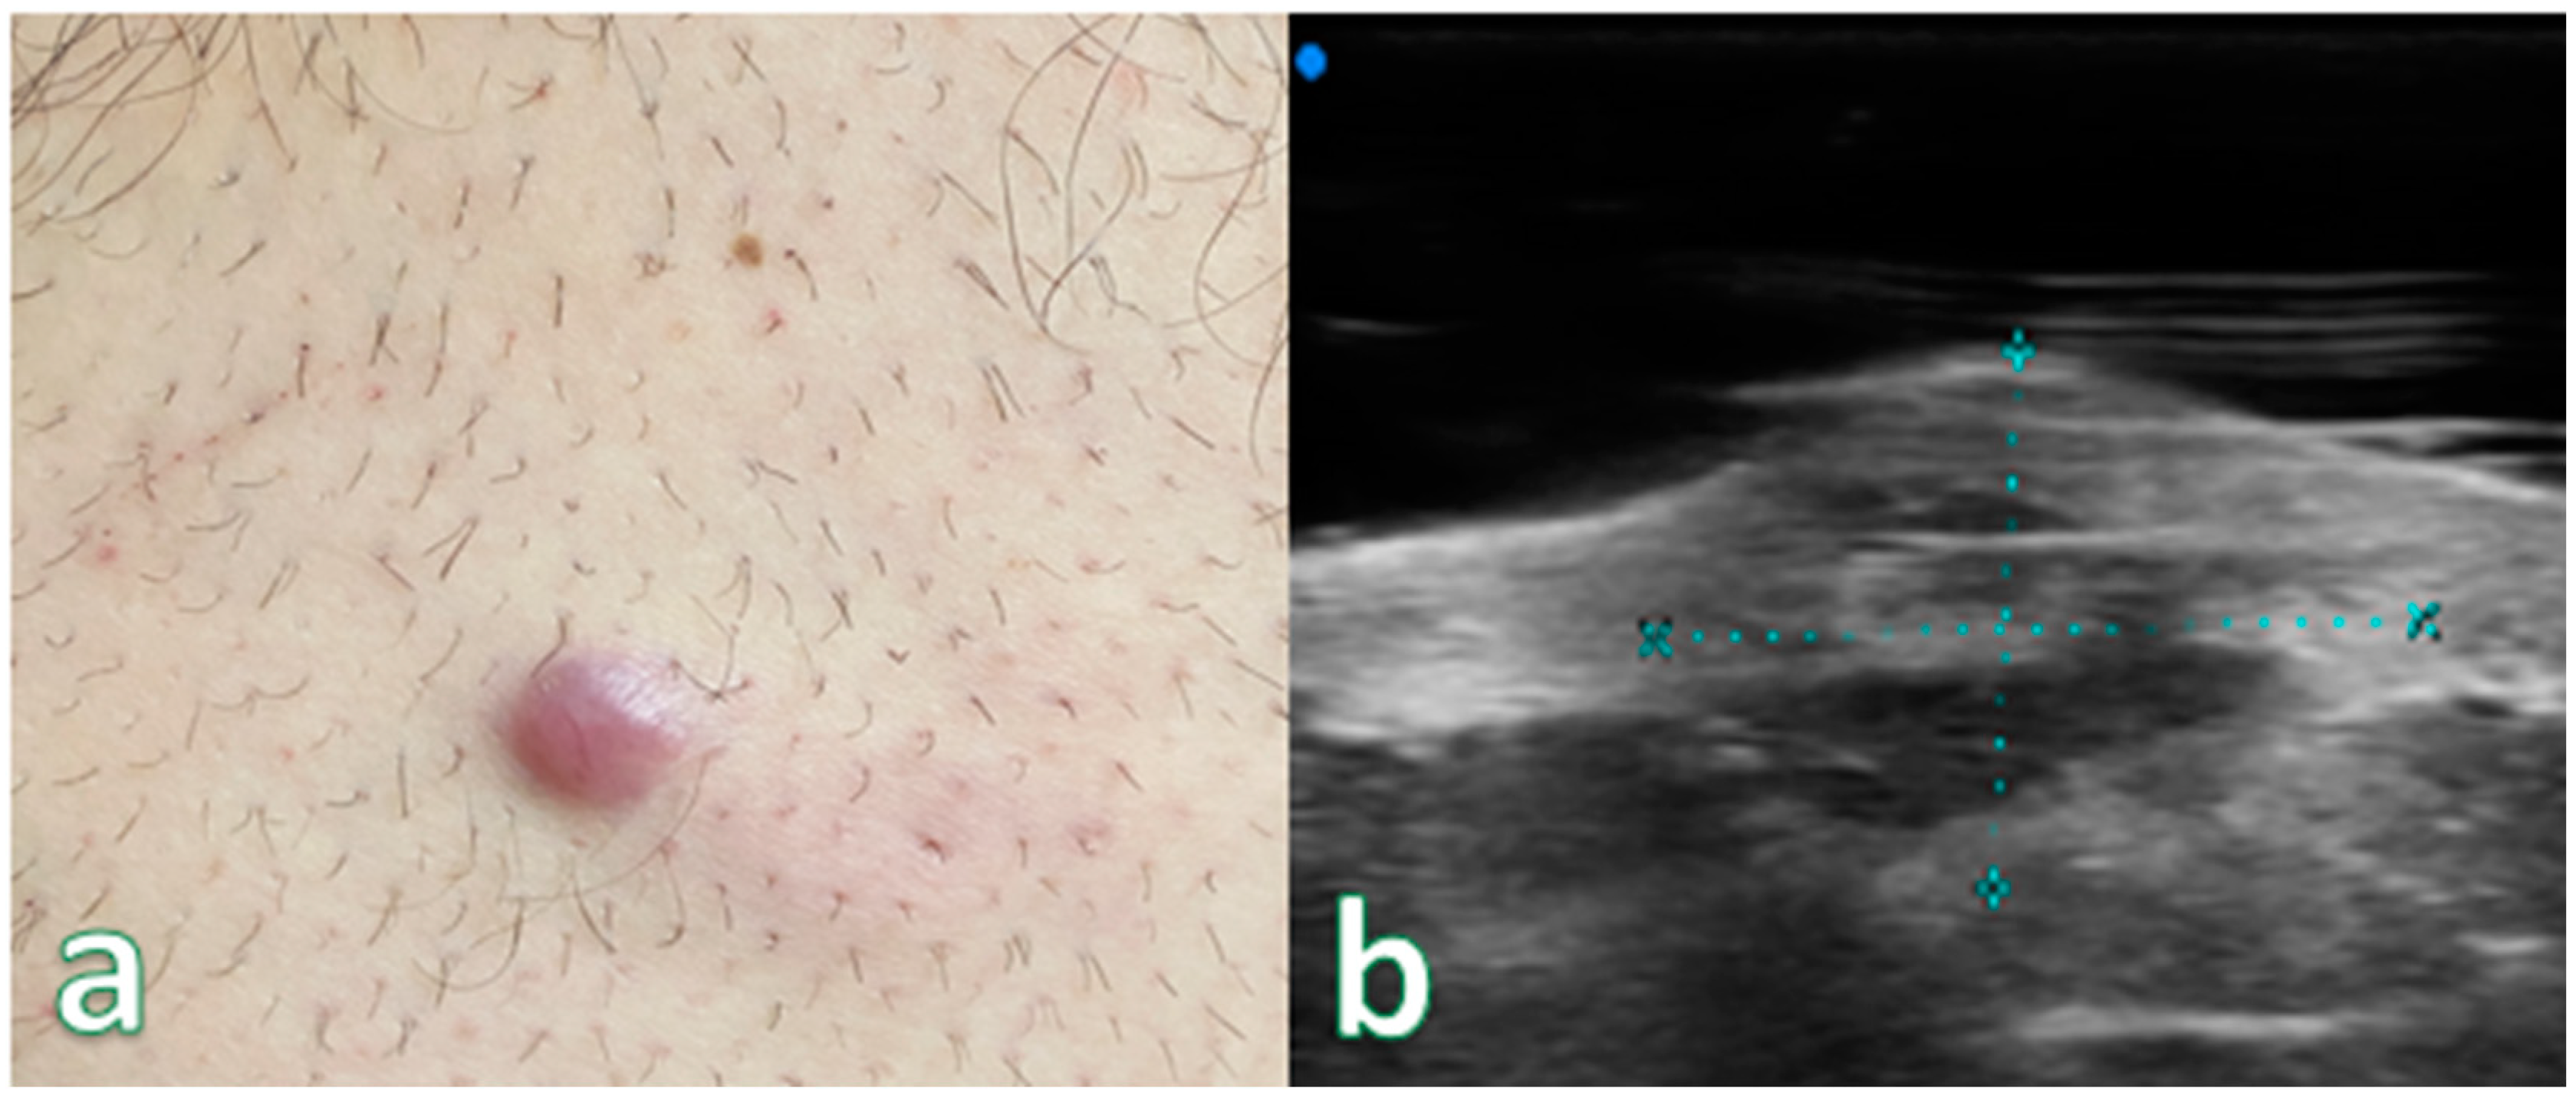

Single or multiple hypoechoic nodules (Figure 2) with focal epidermal–subepidermal involvement, featuring regular margins without peripheral infiltration, were typical of B-cell lymphoma (Figure 3 and Figure 4).

Figure 3. (a) Reddish nodular skin lesion without signs of flogisis in the anterior region of the right leg. (b) Examination performed with a very high-frequency ultrasound probe at 50 MHz showing iso-hypoechoic lesion with irregular and hyperechoic margins infiltrating the epidermis and the subepidermal layer highlighted with dashed blue line. Final pathologic assessment revealed to be a B-Cell Lymphoma.

Figure 4. (a) Nodular skin lesion without signs of flogisis in the right deltoid region. (b) Exam performed with a very high-frequency ultrasound probe at 50 MHz: Iso-hypoechoic lesion with irregular and hyperechoic margins infiltrating the epidermis and the subepidermal layer. Pathologic Assessment revealed B-Cell Lymphoma.